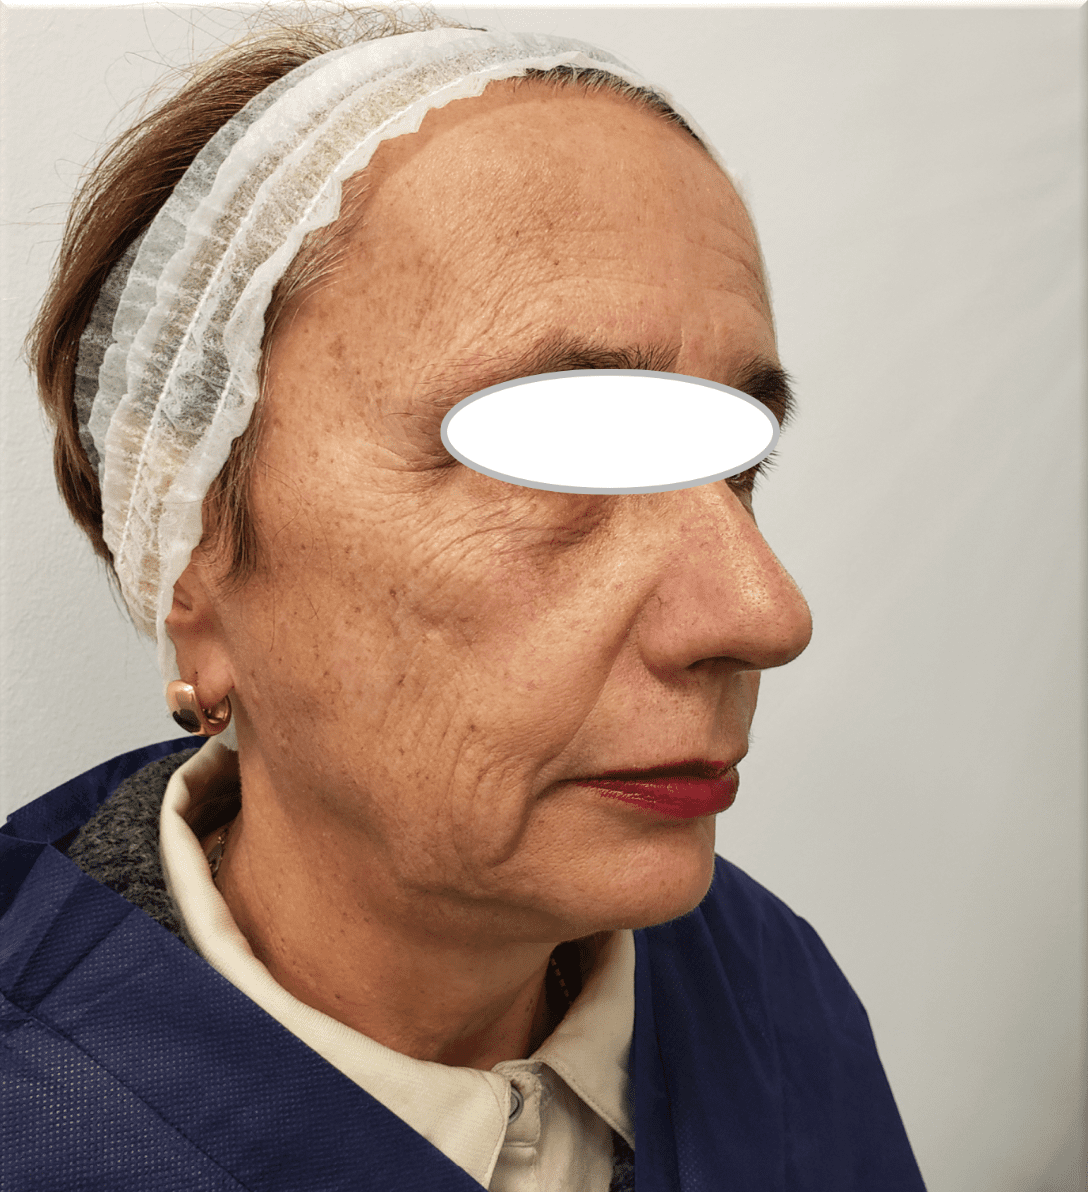

Ultherapy

Before

After